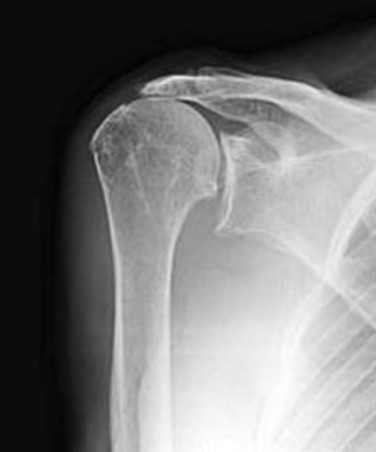

A rotátorköpeny artropátia, vagyis a krónikus rotátorköpeny hiány következtében kialakuló ízületi kopás fájdalmat és funkcióvesztést okoz, jellemzően 60 év feletti korosztályban. A passzív mozgás jellemzően megmarad, de az aktív fej feletti mozgás korlátozott. Ha a mozgás nem korlátozott, többnyire gyengeség akkor is jelentkezik. Ez az állapot éjszakai fájdalomhoz és a fej feletti tevékenységek során nehézségekhez vezet, a hajfésüléstől kezdve a sportokig, mint például a tenisz vagy a golf. A diagnózis a legtöbbször egyértelmű a röntgenfelvételek alapján, amelyeken csökkent ízületi rés és a felkarcsont fejének vállcsúcs irányába történő elmozdulása ábrázolódik.

Az ép rotátorköpeny egyik fő feladata, hogy a felkarcsont fejét az ízületi tányér közepén tartja. Nagyméretű, régóta fennálló rotátorköpeny szakadás ezt az egyensúlyi helyzetet megzavarja és a humerus fej decentralizáltá válik. A rotátorköpeny funkciójának elvesztése lehetővé teszi, hogy a deltoid izom felfelé húzza a felkarcsont fejét, ami hosszú távon az ízület kopásához vezet.